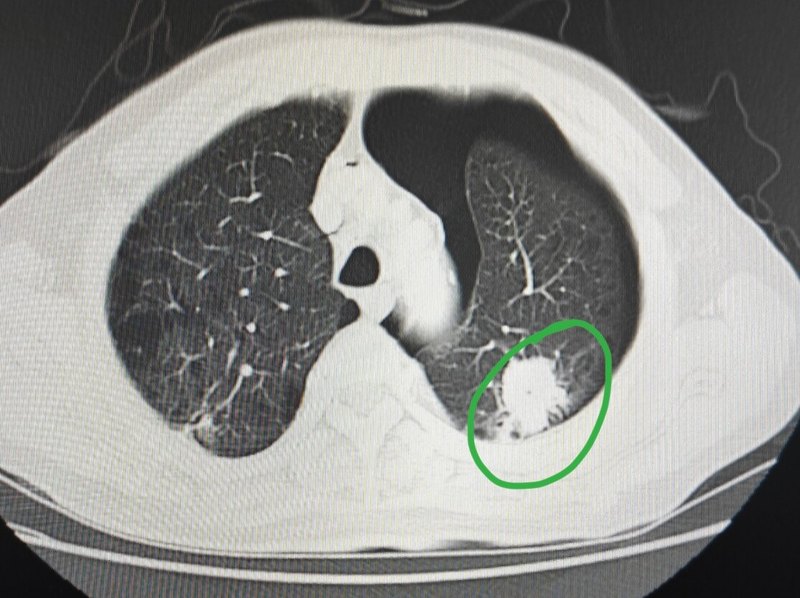

肺結(jié)節(jié)做穿刺,氣胸是最常見的并發(fā)癥。在做穿刺之前,醫(yī)生會把穿刺過程中以及穿刺后所可能面臨到的問題向患者以及家屬進(jìn)行充分的交代,包括氣胸、出血以及感染等等都會涉及到。有一位70歲的男士在另一家三甲醫(yī)院住院,他肺里有一個接近三厘米的結(jié)節(jié)。那家醫(yī)院經(jīng)過系統(tǒng)檢查,覺得他不符合手術(shù)條件,給他安排做了穿刺取病理,讓他保守治療。穿刺后的病理顯示是一個肺鱗癌,他的家屬帶著片子到我們醫(yī)院來,想問問這種情況能不能手術(shù)?大家看這位患者穿刺后的片子,他的肺結(jié)節(jié)在左肺上葉,比較貼近胸膜,在左側(cè)胸腔里面,CT顯示還有黑色的,那就是空氣,這就是穿刺后形成的氣胸。大家覺得肺結(jié)節(jié)穿刺后出現(xiàn)了氣胸,患者會有什么不舒服的癥狀么?這要看氣胸的多少了,如果不是特別多,患者自己沒有任何不舒服的感覺,這位患者雖然胸腔里邊有氣胸,但他自己沒有不舒服。